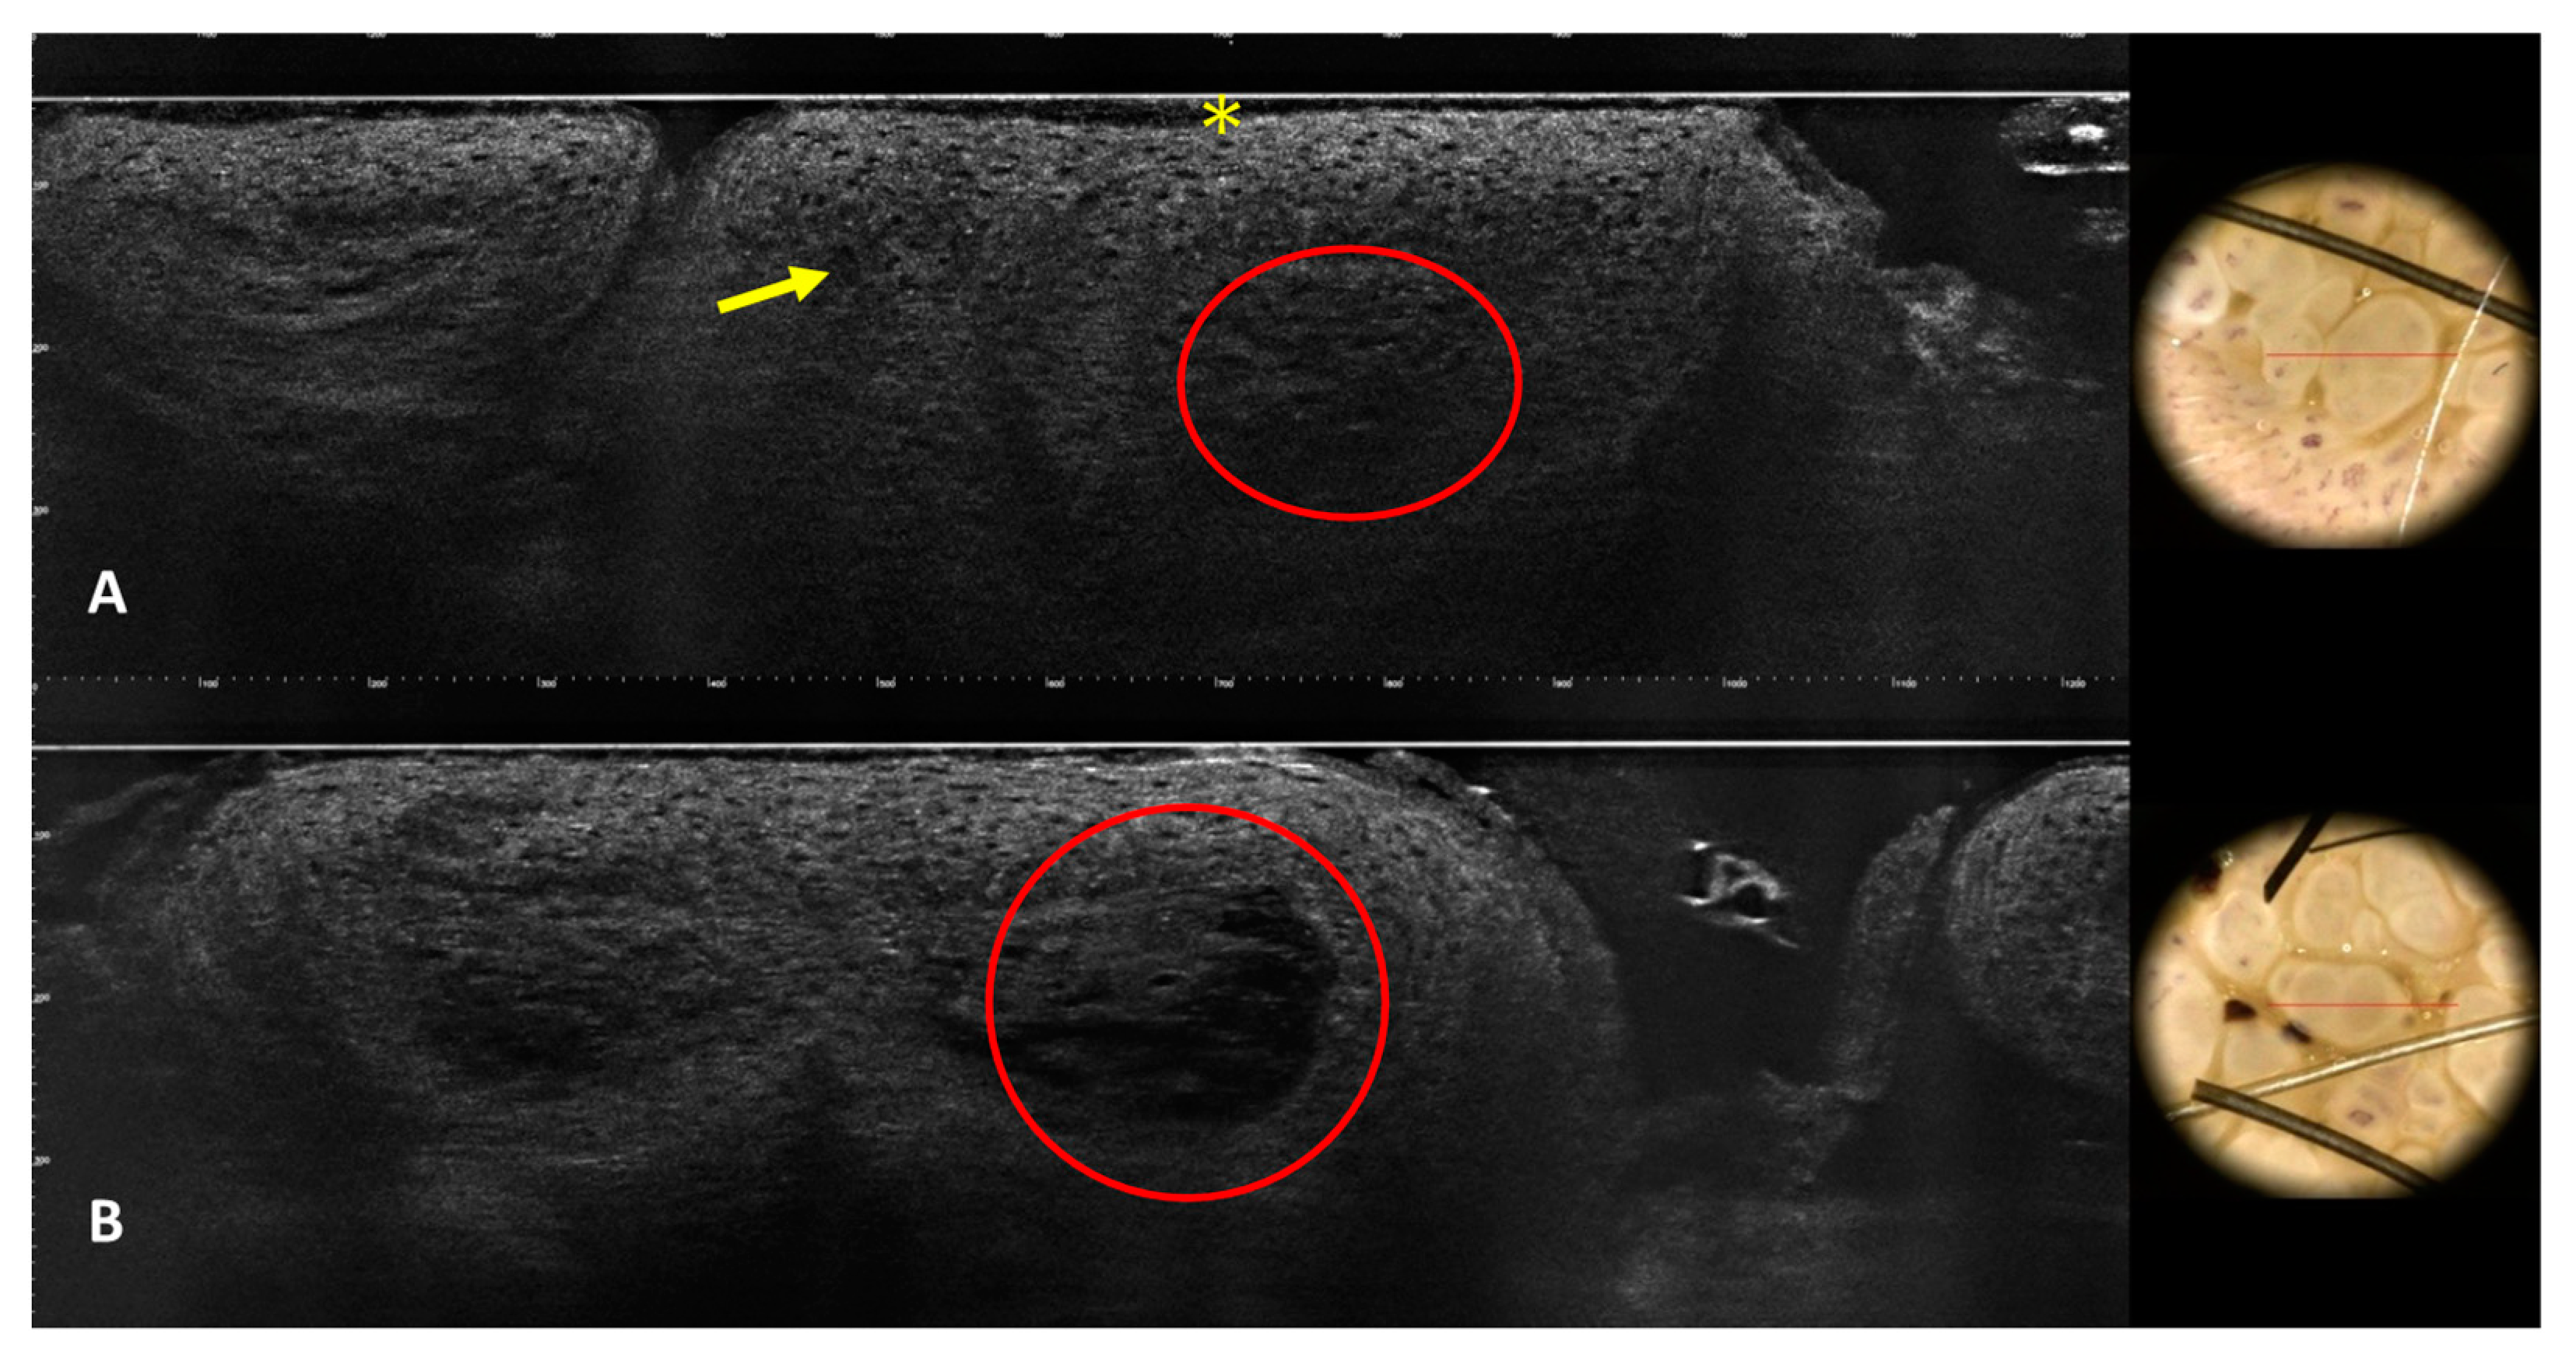

3.1. Images of the Genital Warts